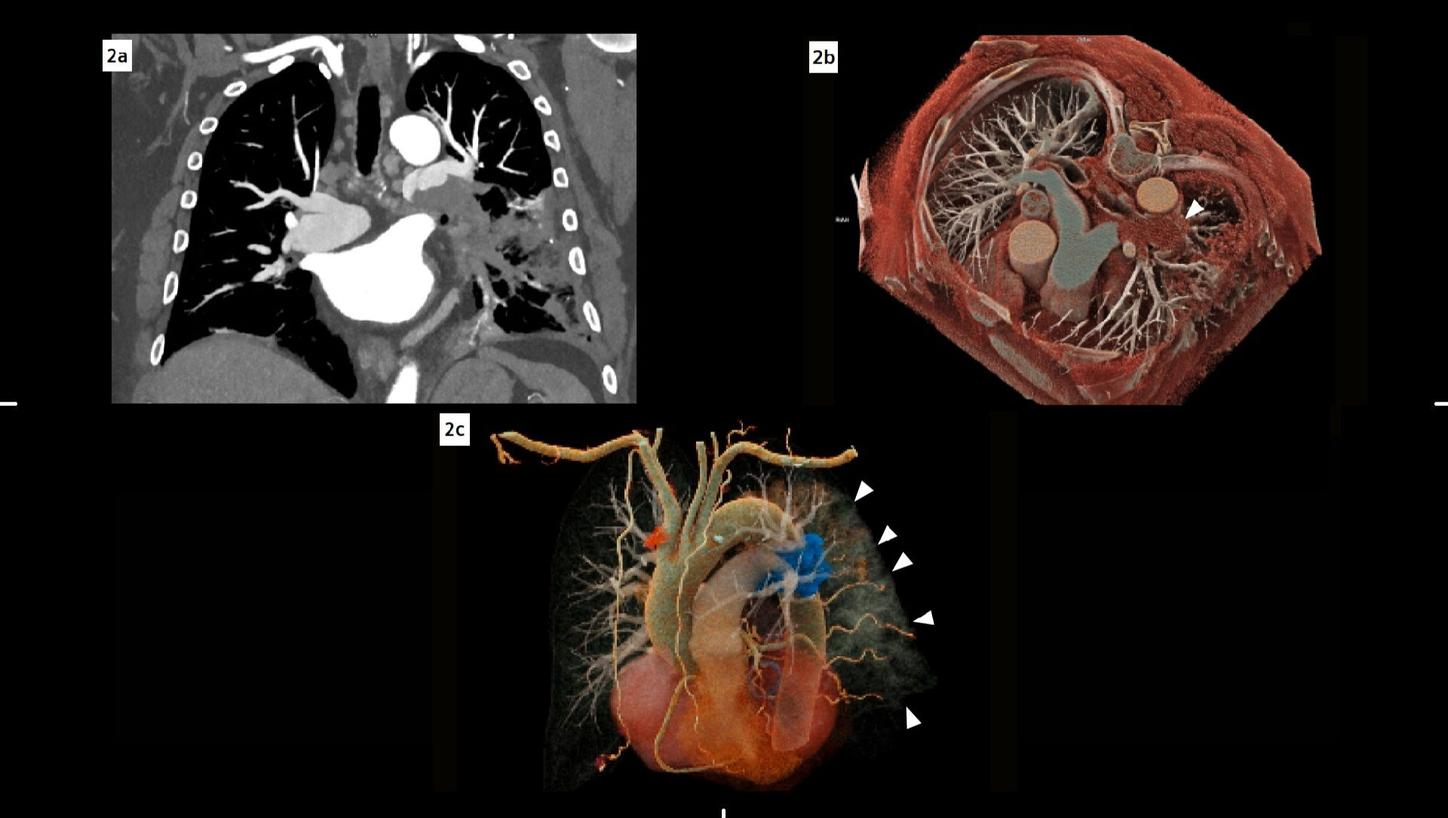

Fig. 2: Coronal maximum intensity projection (MIP) image of the pulmonary vasculature (a) demonstrates a filling defect in the lower part of the left pulmonary artery. Volume rendering technique (VRT) reconstructions (b, c) depict the pulmonary vessel arborization: In (b), a cross-sectional view, the filling defect is visible in the left pulmonary artery (arrow). In (c), an oblique view, the embolus is highlighted in blue, while the consolidations in the lung can also be appreciated (small arrows).

The fine spatial detail (0.4 mm slice thickness) enabled an accurate evaluation of the coronary arteries to rule out severe CAD (as part of the differential diagnosis of chest pain) (see Figure 1). The use of advanced image reconstruction algorithms, such as ZeeFree, combined with the preview series function, resulted in only minor motion artifacts on the acquired scans, despite the high heart rate variability (Minimum: 86, Maximum: 158, average: 110). Detector-based quantum spectral imaging capabilities (lung analysis reconstruction) made it impressively fast to detect lung perfusion deficits caused by the PE and aided further therapy decision-making by down-grading disease severity. A fair dose length product (636 mGy*cm) was achieved during the chest CTA, utilizing the NAEOTOM Alpha.Prime CT scanner with an optimized protocol, serving as a true “one-stop-shop” TRO-CT examination.